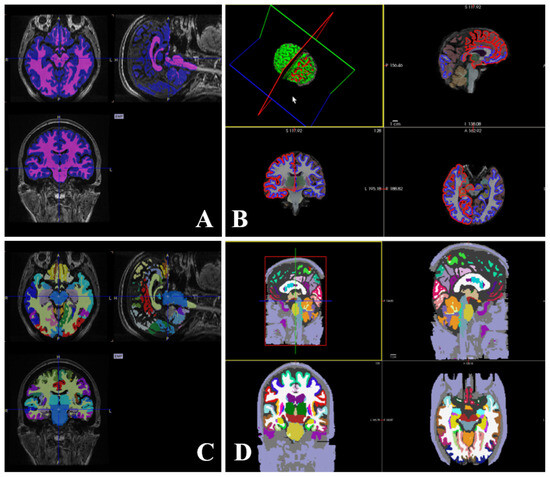

2.2. Image Scan

2.3. Images and Statistical Analysis